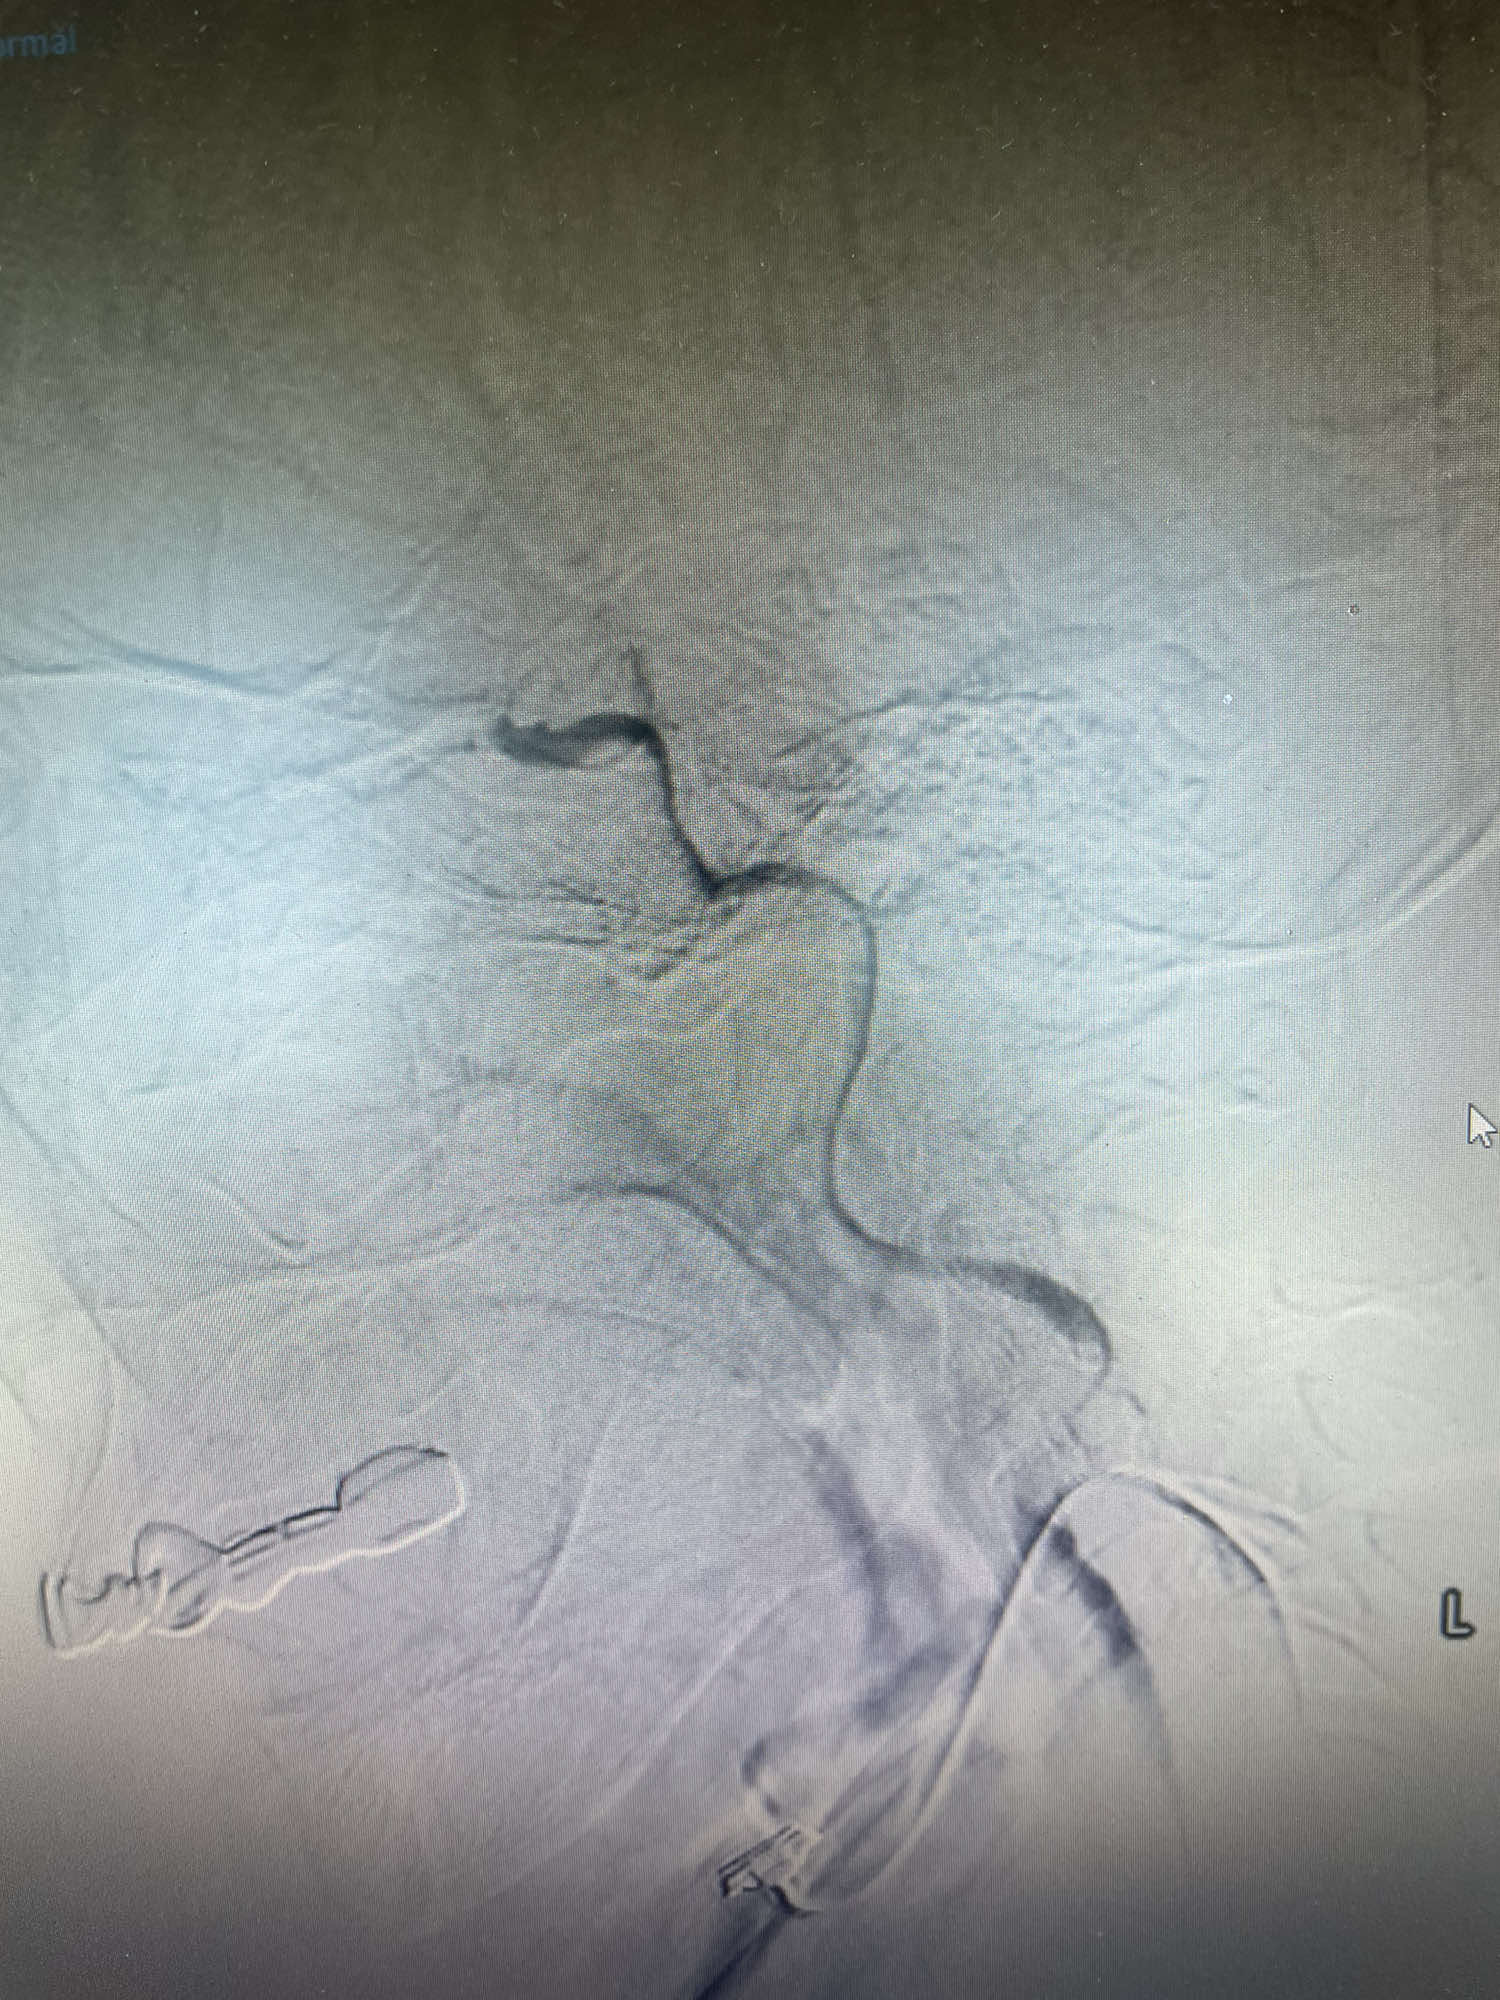

术后复查脑血运重建满意